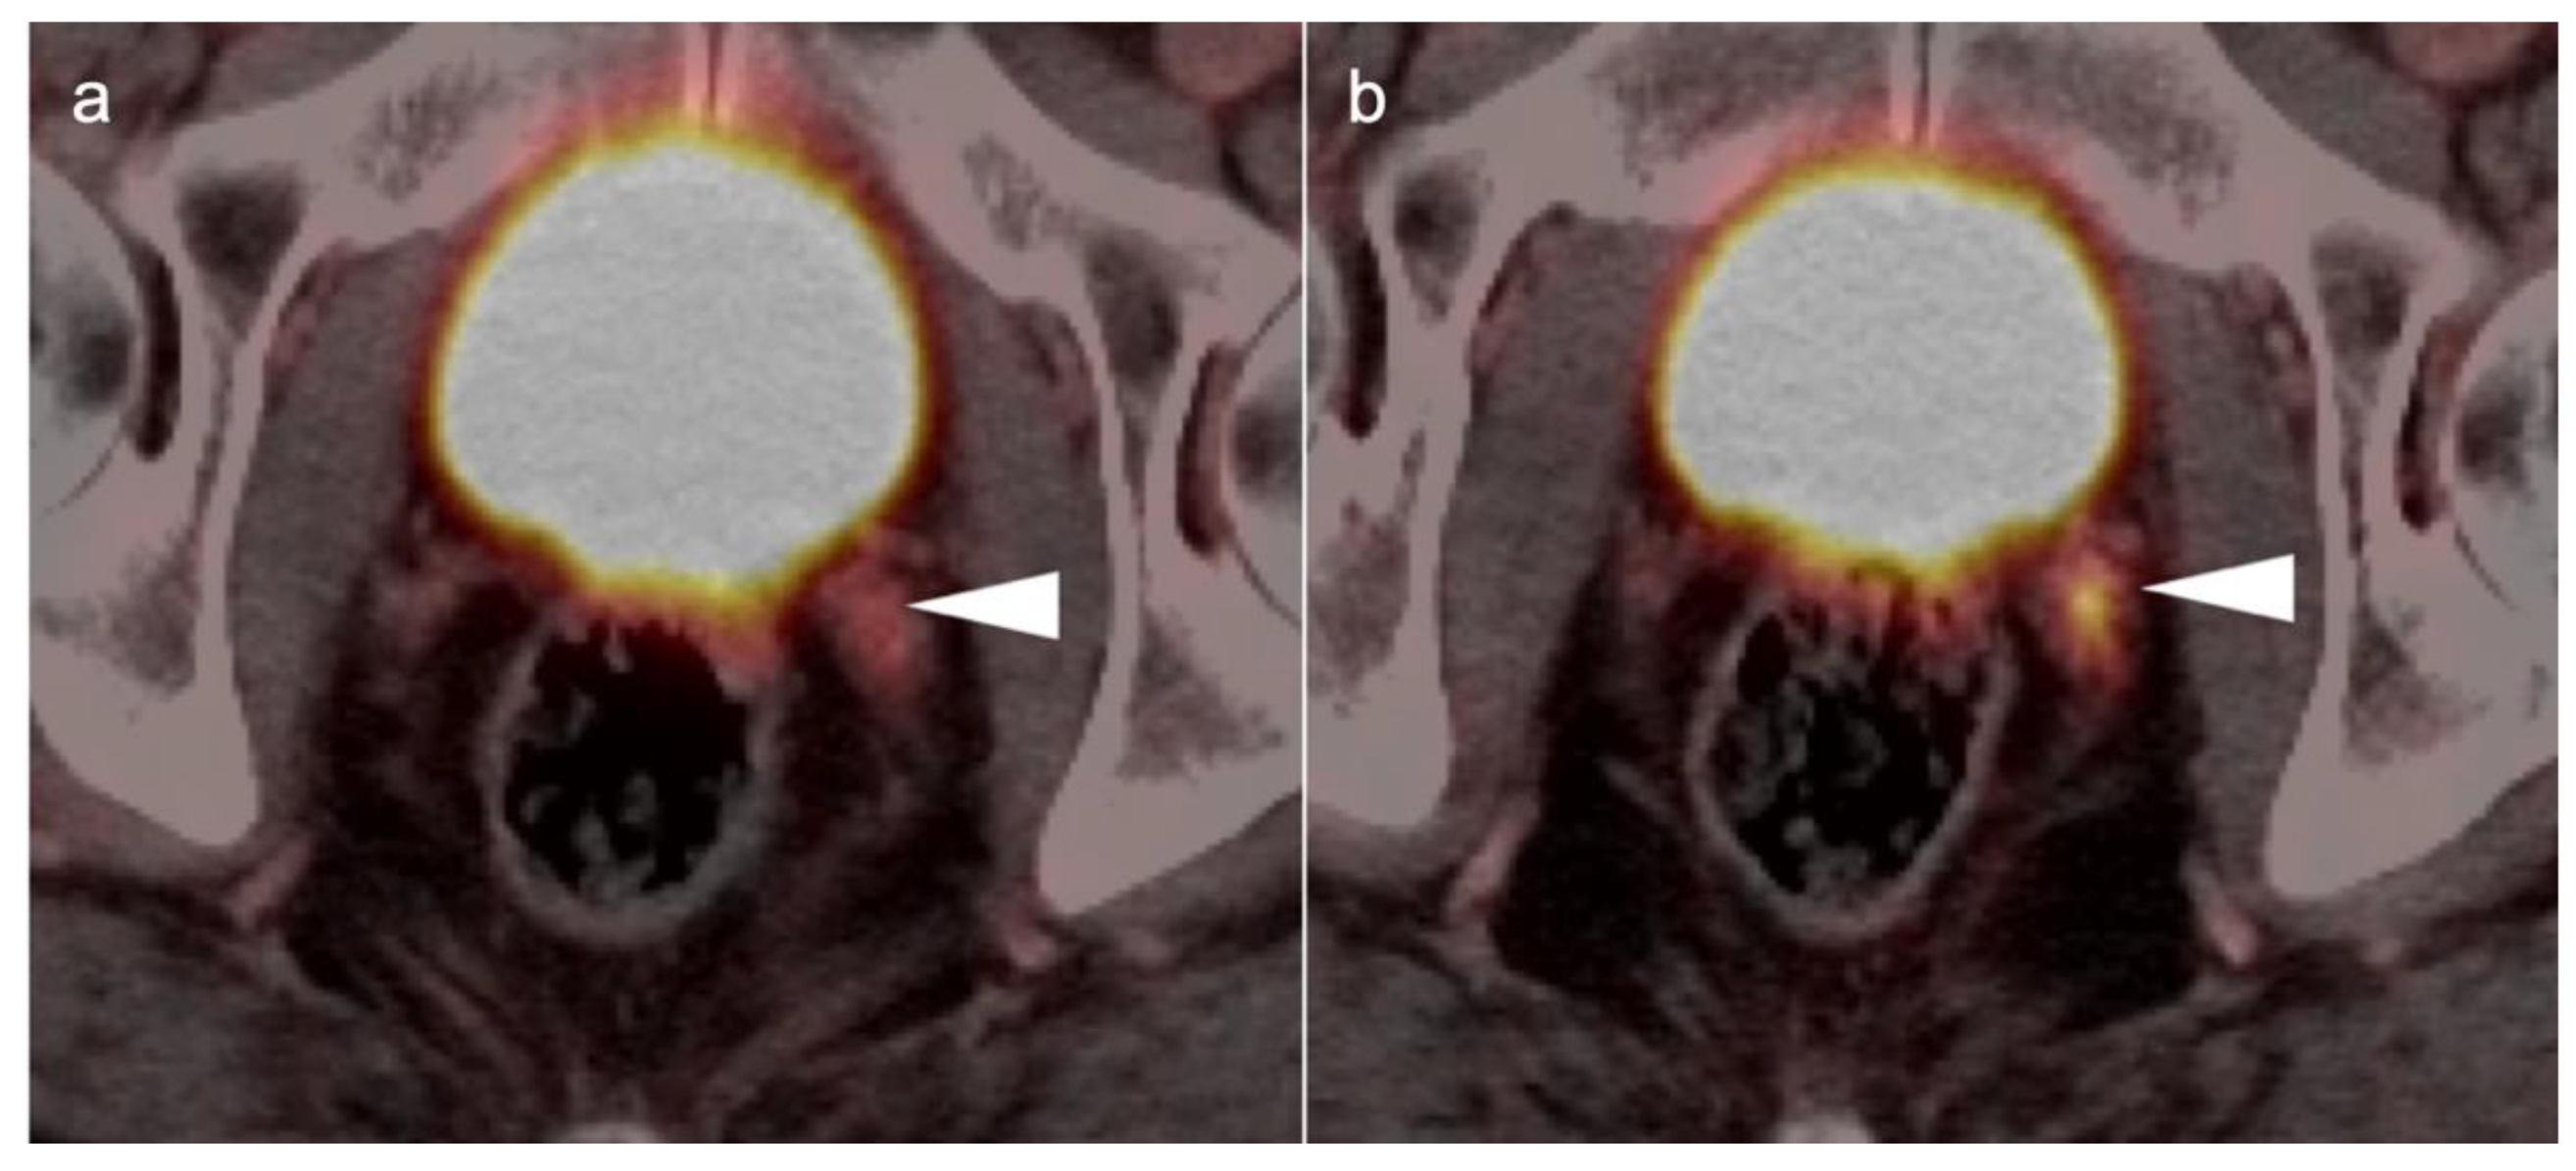

3.1. Prostate Cancer

3.2. Urothelial Carcinoma